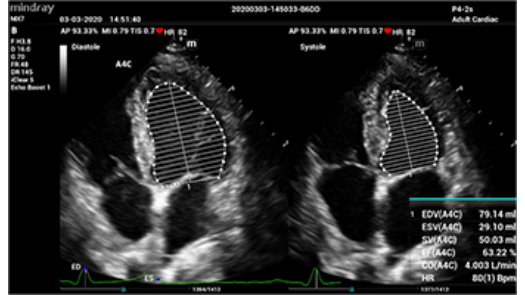

Auto EF

- Автоматическое распознавание A2C или A4C

- Автоматическое распознавание границы эндокарда

- Автоматическое распознавание диастолических и систолических значений